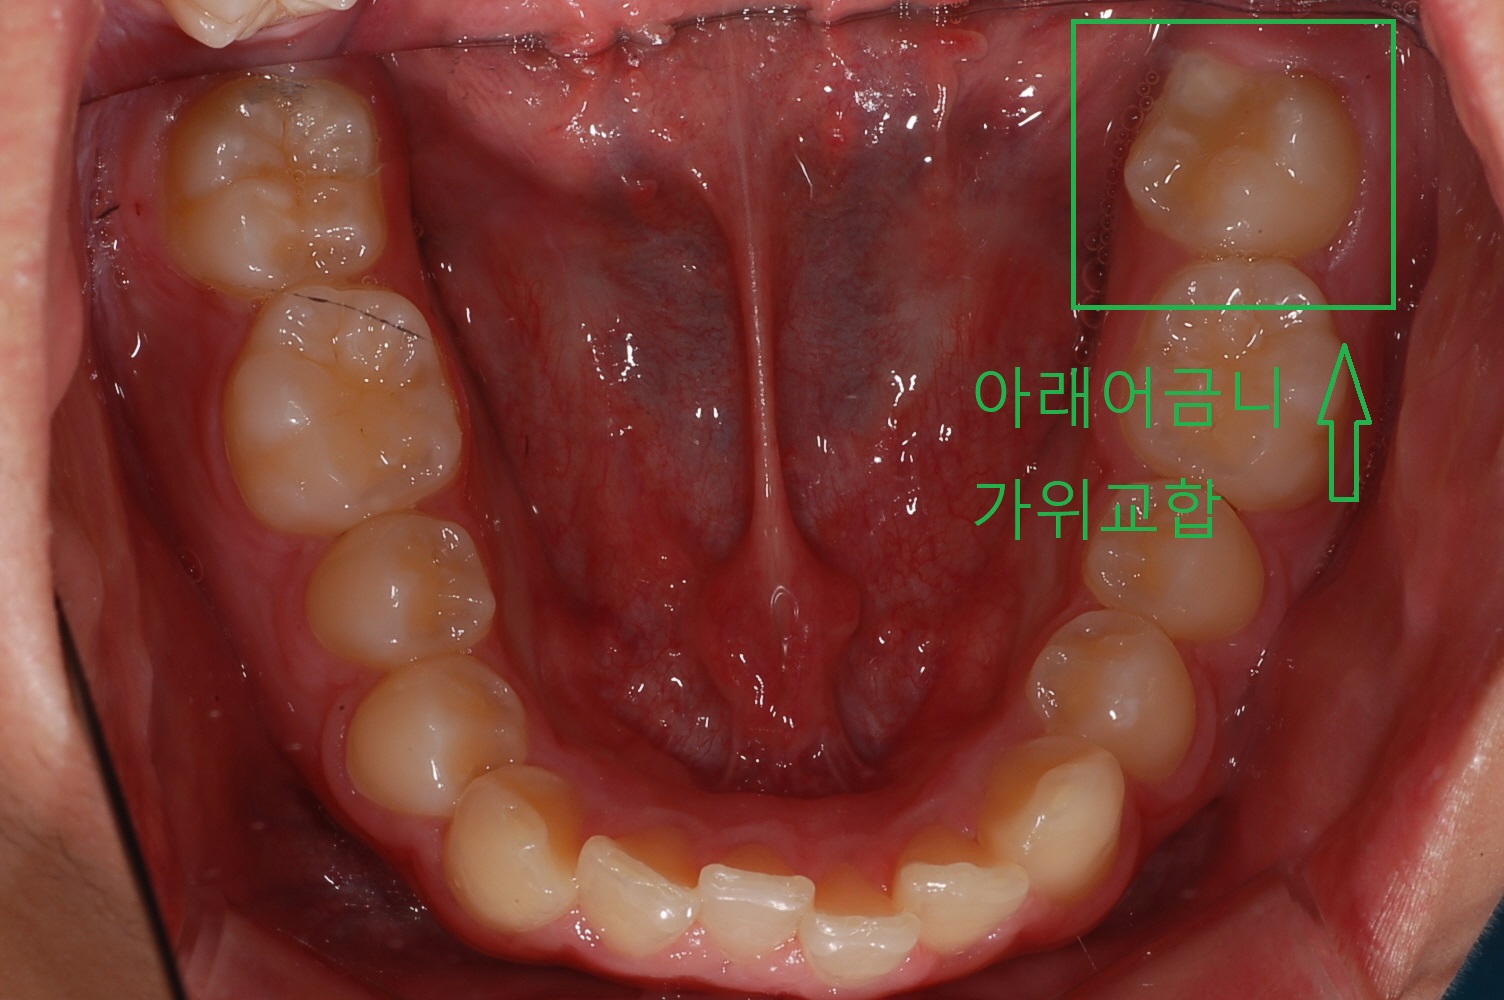

아들치아 교정하면서 공부도 참 많이 하게 되네요. 영구치의 치아상태가 위, 아래 어금니가 누운 상태로 지냈습니다. 이것을 가위교합이라고 합니다.

집에서 쓰는 가위 아시죠? 이처럼 위,아래 어금니가 맞지 않은 상태를 가위교합이라고 합니다.

위,아래 어금니가 안.밖으로 쓰러져 있는 상태입니다. 이 상태로 계속 두면 부정교합 시간이 길어져 치아가 더욱 틀어짐이 심해지며 결국은 발치를 빨리 해야 될 상황이 오게 됩니다.

◎ 아들치아교정 전 상태확인 (가위교합사진)

- 「윗 어금니 가위교합 1개」

- 「아래 어금니 가위교합 1개」